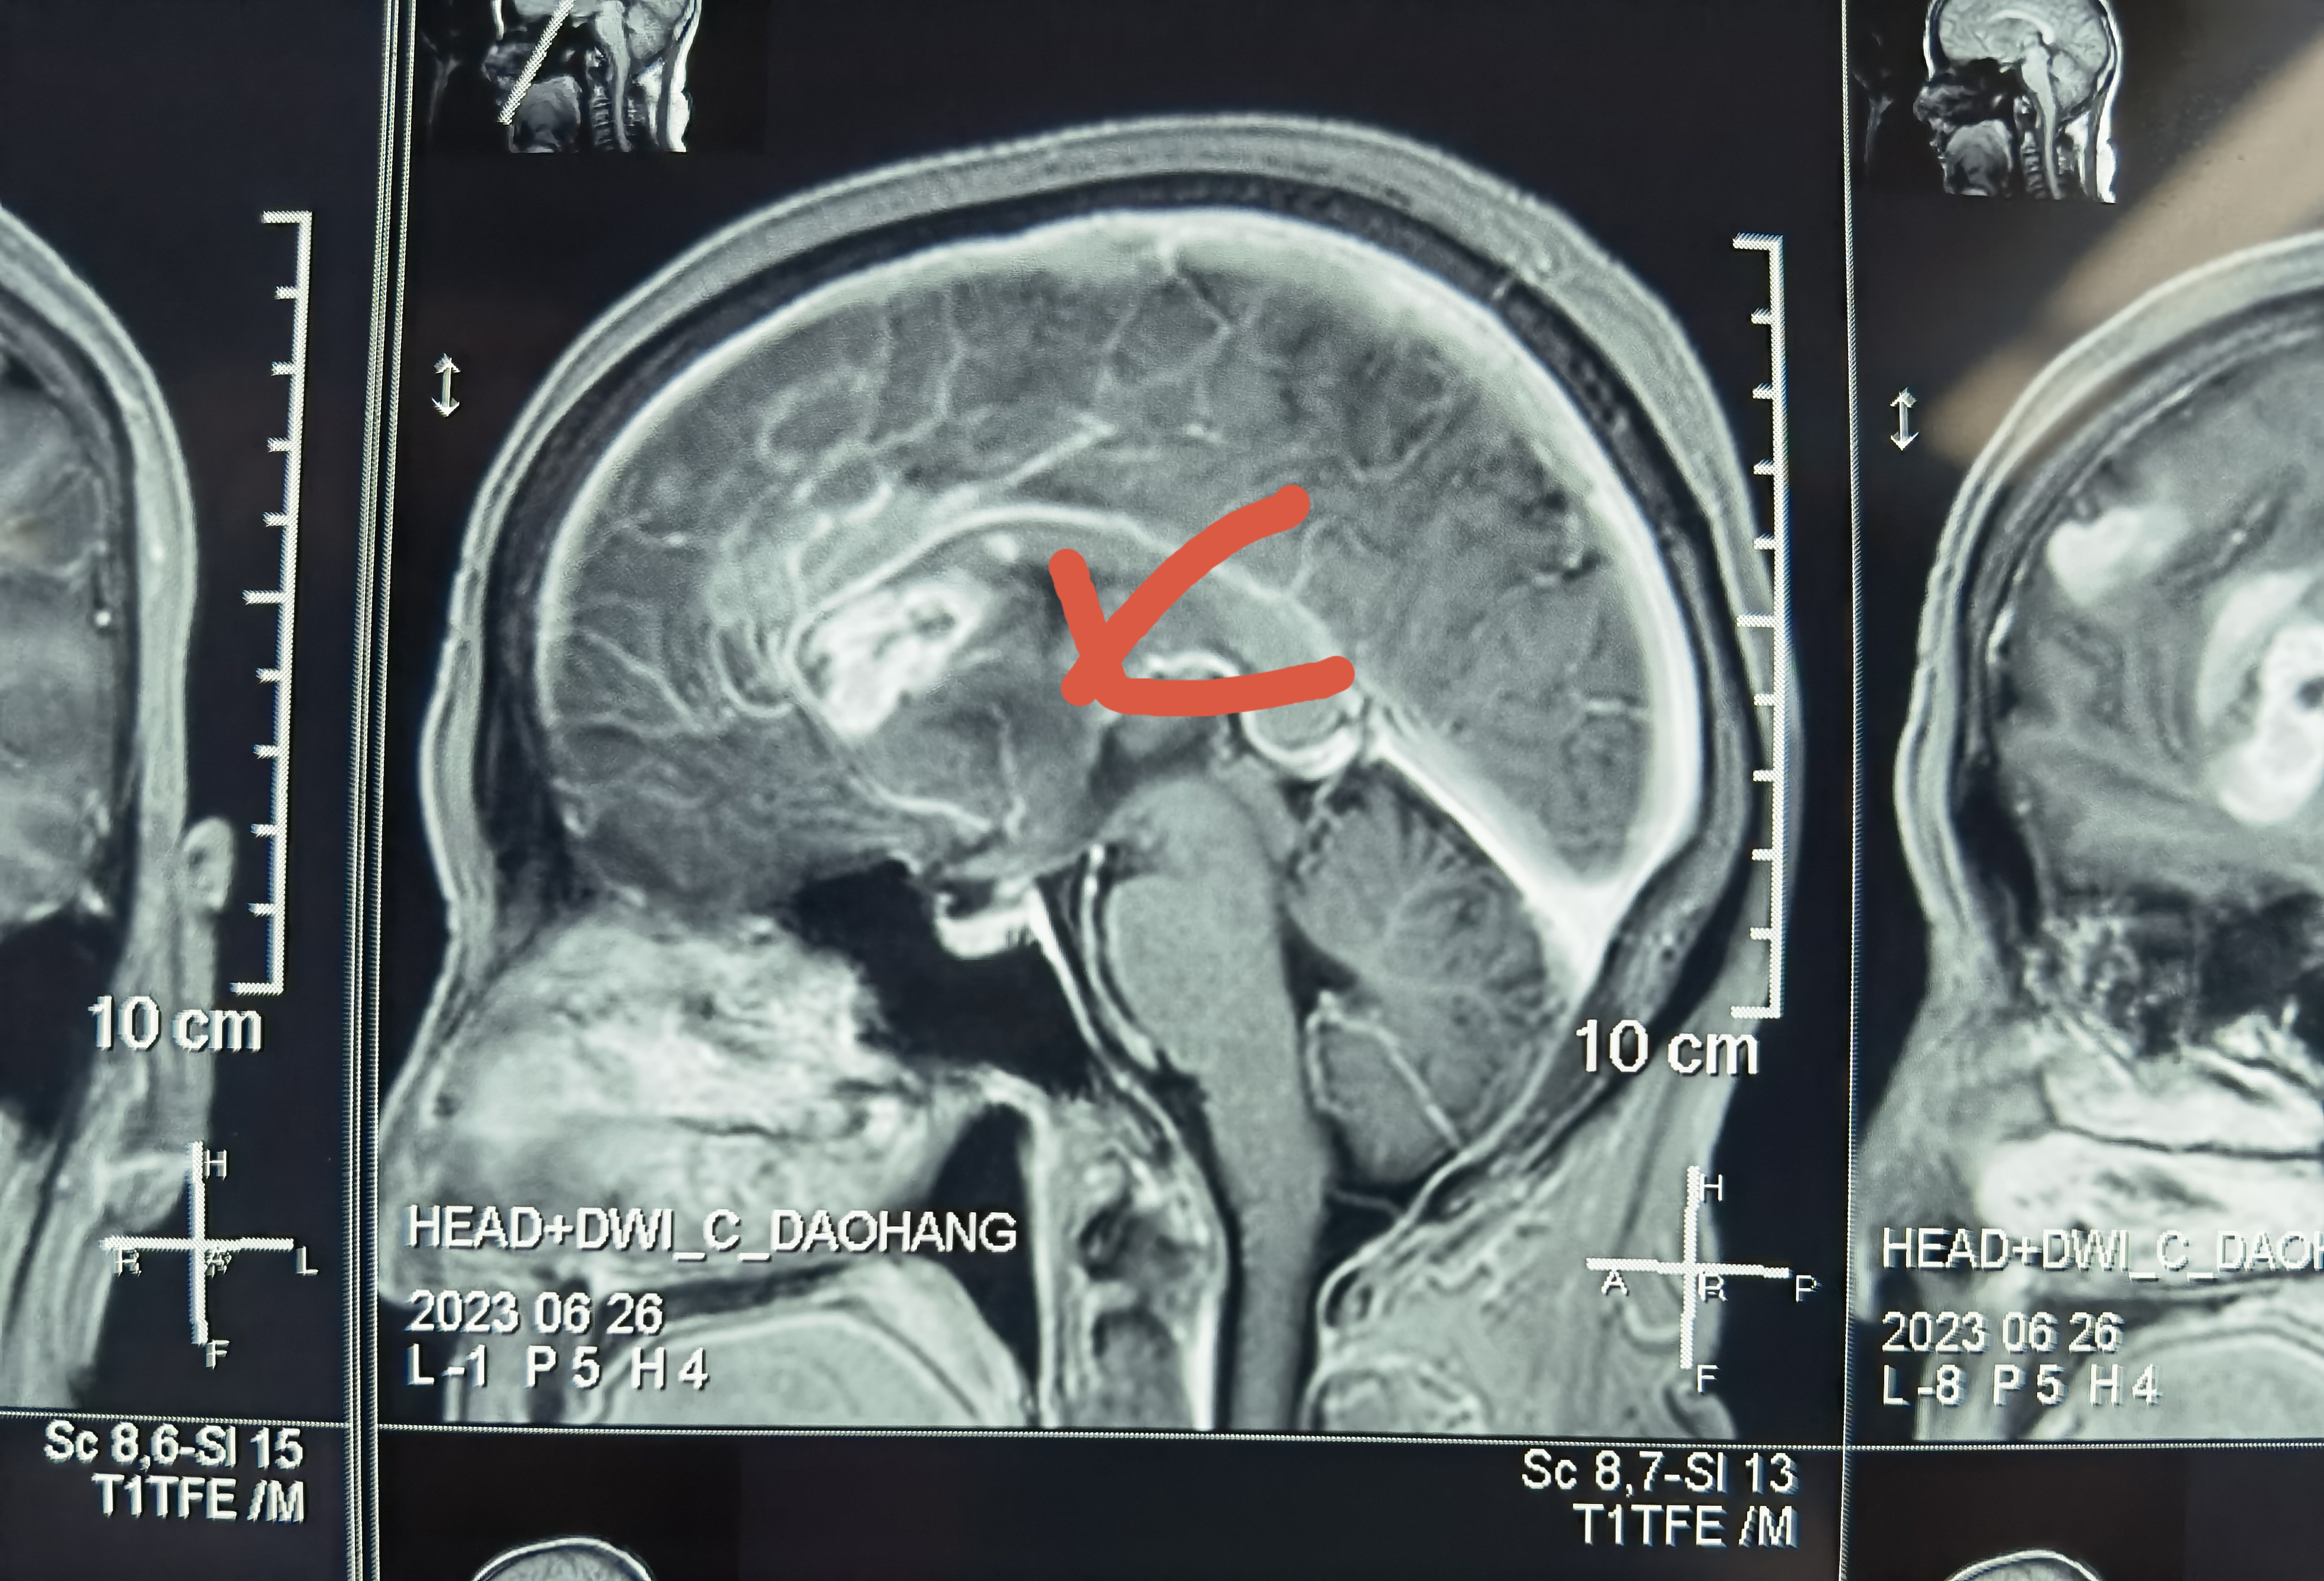

术前增强核磁:

片子可见肿瘤多中心, 累及范围广,包括胼胝体膝部,穹窿体,下丘脑,双侧额叶,左侧脑室前壁。

由于术中见下丘脑部位肿瘤灰红色鱼肉状,质地软,吸除过程中有下丘脑穿支损伤,可能会造成术后昏迷!

肿瘤血运极其丰富,必须先行离断来自胼周动脉及胼缘动脉的供血动脉,才能有效减少血运,在相对清晰的术野下切除肿瘤。术中双侧胼周胼缘动脉及分支均得到有效保护。

累及胼胝体膝部肿瘤是能够达到影像学意义的全切的,术后病人淡漠,反应迟钝症状往往较轻。此例患者考虑下丘脑损伤所致意识水平较差。